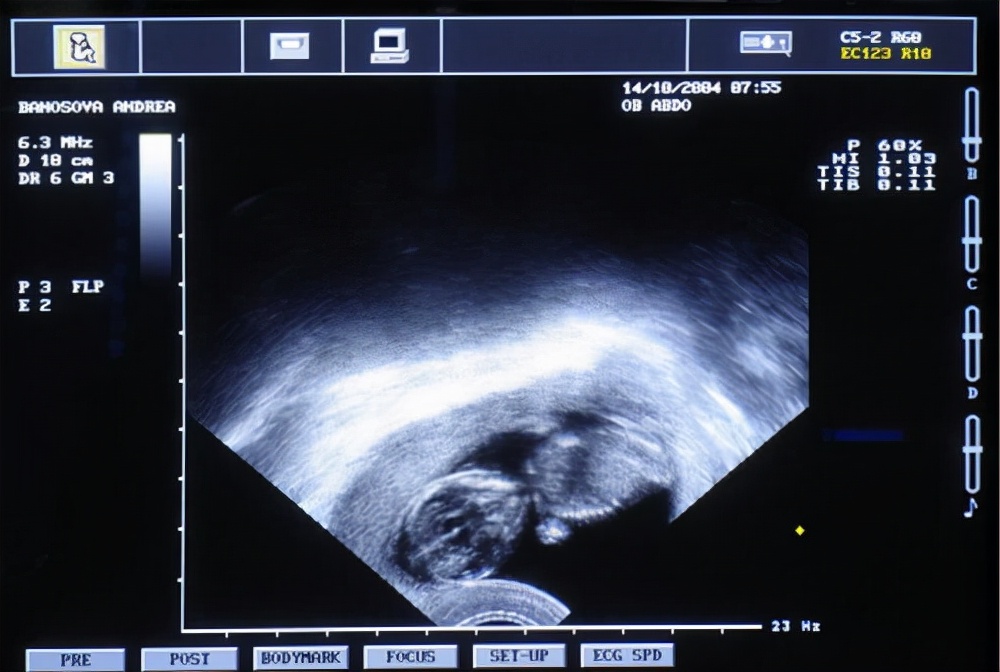

操作时,医生用探头旋转、推位、倾斜探查汤女士的子宫,然后一副非常清晰的子宫B超图就出现在了医生身边的电脑仪器上。顺便,医生还帮汤女士检查了一下卵巢及其它器官。不一会,医生就把探头取了出来,结束了这次诊断。

可以说,阴式B超是目前临床诊断女性生殖疾病最有效的手段,能清晰检测到女性子宫、卵巢、阴道的情况。